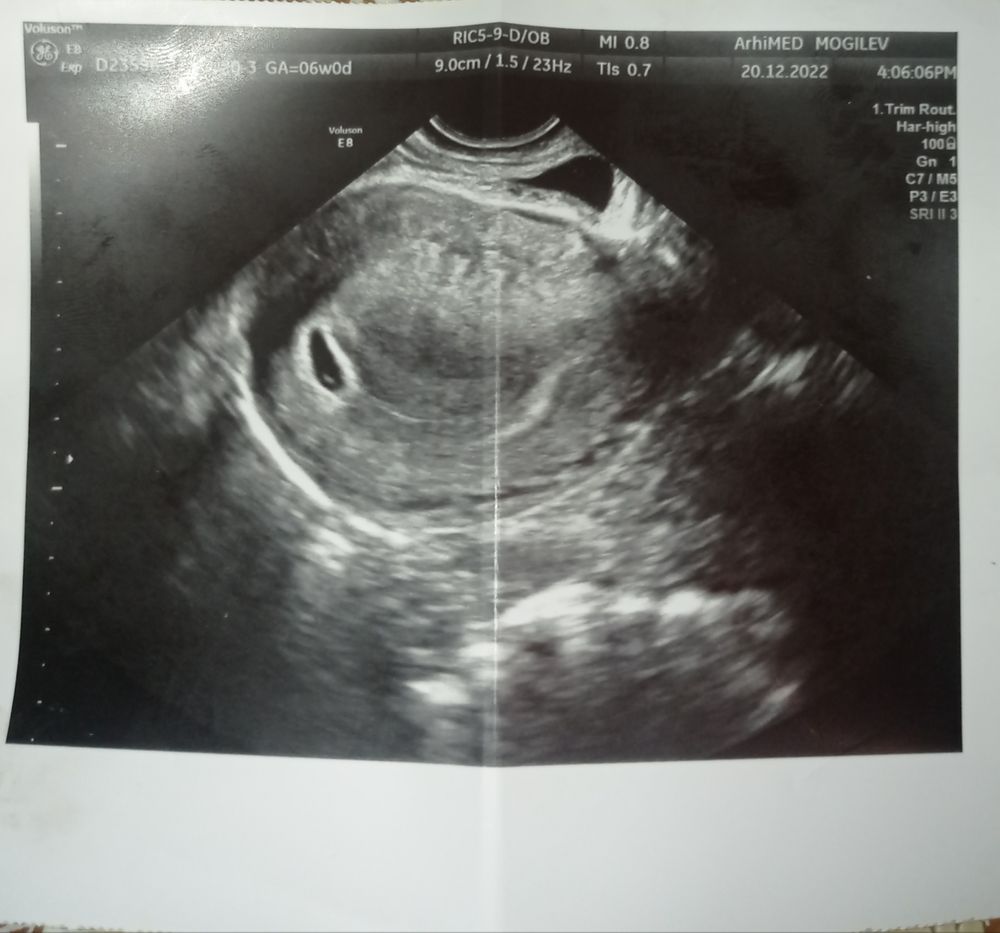

Узи 6 недель нет сердцебиения

Узи 6 недель нет сердцебиения 119 фотографий